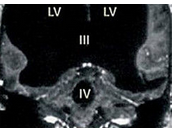

光片显示,该男子75%的脑组织已消失不见。

中新网8月18日电 据英国媒体报道,法国一名男子曾因腿部疼痛去医院检查,医生却找不出病根。在对其进行了全身体检后才发现,原来这名男子的腿疼是由脑部病变引起的,而该男子的大脑只剩下正常人大脑体积的一半都不到了。

报道称,这件事其实发生在2007年,近日由著名医学杂志《柳叶刀》披露。这名大脑神秘消失的男子当年44岁,医生在对其进行脑部检查后发现,他左右半脑上的额叶、顶叶、颞叶及枕叶都萎缩了。

在对这名男子的病史进行详细调查后发现,原来他童年时患有后天脑积水症。但在他14岁时,经历了分流术,随后的30年,这名男子和家人都以为完全康复了。但其实他的大脑还是在病变,最终,脑内的积水损坏了脑组织,导致其大脑50%至75%的部分都消失了。